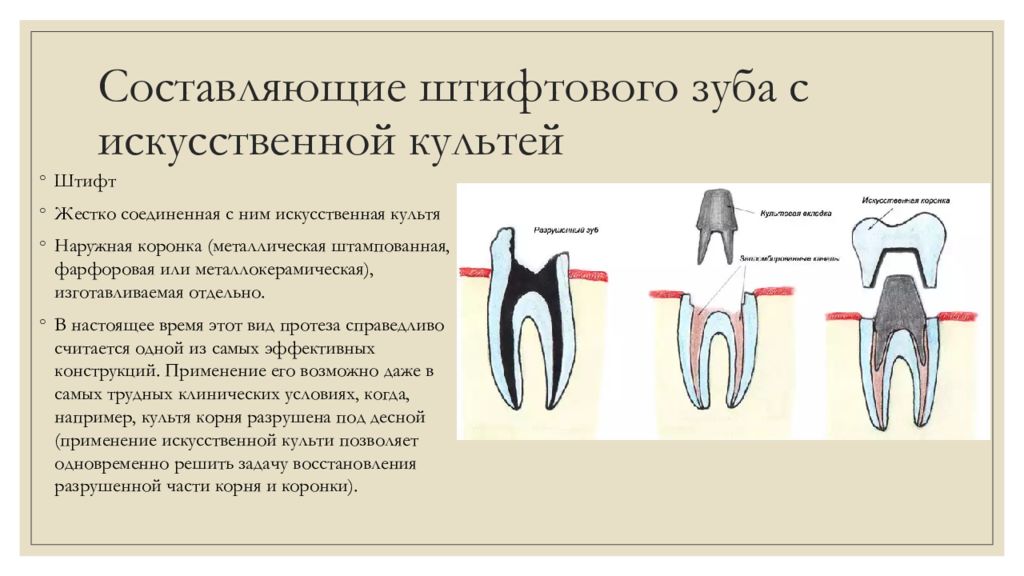

Культя зуба это

Культя зуба это 106 фото